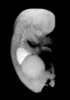

Carnegie Stage 23 (56 post-ovulatory days)

Most embryos at stage 23 are approximately 56-57 postovulatory days old and measure 23-32 mm in length. Distinguishing criteria for this stage include fusion of the eyelids at the medial and lateral margins, clear distinction of the subdivisions of the upper and lower limbs, the forearms appear at or above the level of the shoulders, the superficial vascular plexus of the head is very close to the vertex, and the external genitalia are well developed but not always sufficiently to distinguish the embryo's sex.

(NOTE: These specimens are late stage 23.)